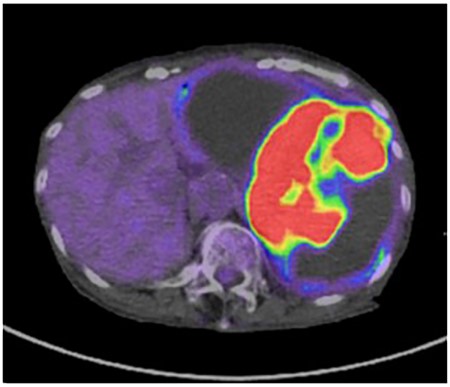

A 79-year-old woman was referred to our hospital because of nausea for about 3 months. Her medical and family histories were unremarkable. On admission, her vital parameters were as follows: temperature, 36.6°C; blood pressure, 120/84 mmHg; heart rate, 72 beats per minute (regular); respiratory rate, 15 breaths per minute and oxygen saturation, 99% on room air. Physical examination revealed a soft mass was palpable in the left upper quadrant. Laboratory investigation revealed slight anemia (hemoglobin: 10.3 g/dL), but other results, including the serum tumor markers carcinoembryonic antigen, cancer antigen 19-9 and cancer antigen 125, were within normal ranges. Abdominal computed tomography (CT) revealed a large tumor with multilocular cystic and solid components, and only a small amount of normal splenic parenchyma remained. And the tumor extensively compressed the stomach ventrally. The boundary between the pancreatic tail and the hilum of the spleen was somewhat unclear, but no obvious mass lesion was observed in the pancreas (Fig. 1A and B). On magnetic resonance imaging, the solid part included an uneven high signal on T1-weighted images and a low signal on T2-weighted images, suggesting internal bleeding (Fig. 2A and B). On a positron emission tomography scan, 35.9 points of 18F-fluorodeoxyglucose accumulation of standardized uptake value showed in the only solid part of the tumor (Fig. 3). Although a definitive preoperative diagnosis could not be made, angiosarcoma originating in the spleen was suspected first, and laparotomy was performed.

The solid part of the tumor has a higher uptake of 18F-fluorodeoxyglucose (standardized uptake value of 35.9) on positron emission tomography, and no obvious evidence of distant metastasis is present.